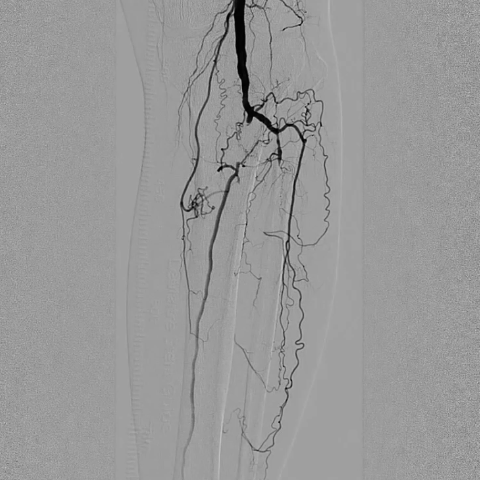

ABI检查(踝肱指数)提示左侧下肢动脉严重狭窄或闭塞。超声提示双侧股总动脉、股浅动脉等多部位动脉内中膜增厚,可见多发斑块;左侧胫腓干动脉、腓动脉及双侧胫前动脉管腔闭塞,左侧胫后动脉及双侧足背动脉依赖侧支血管代偿(流速异常)。

术前CTA进一步证实:左侧胫腓干动脉、腓动脉闭塞,双侧胫前动脉闭塞,病变范围广且涉及多支重要下肢动脉。

术前影像

造影显示左侧胫腓干动脉闭塞,胫后动脉通过侧支循环显影,左侧腓动脉及胫前动脉全程闭塞。